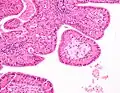

The appearance of this tumor under the microscope is unique. There are cystic spaces surrounded by two uniform rows of oncocytes, which are epithelial cells with abundant, granular, eosinophilic cytoplasm.[7] The cystic spaces have epithelium referred to as papillary infoldings that protrude into them. Additionally, the epithelium has lymphoid stroma with germinal center formation.

Low magnification micrograph of a Warthin tumor arising from the parotid gland.

Histopathology of Warthin tumor in the parotid gland. H&E stain.

Histopathology of Warthin tumor in the parotid gland. Another view of a file "Warthin tumor (1).jpg". H&E stain.

Histopathology of Warthin tumor in the parotid gland. Higher magnification of a file "Warthin tumor (1).jpg". H&E stain.

Intermediate magnification micrograph of a Warthin tumor.